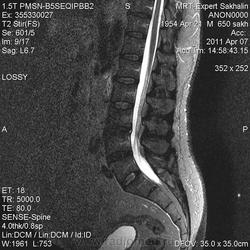

Учитывая, что сигнал подавился на FS, скорее да, жировая дегенерация. В случае гемагиомы с большим содержанием жировой стромы будет ли на FS подавлятся сигнал незнаю. Надо будет выяснить экспериментальным путем. :-)

Жир он везде жир, в том числе и в гемангиоме.

Реконверсия -обратное замещение жирового костного мозга кроветворным при патологических состояниях, сопровождающихся повышением потребности организма в кроветворении.